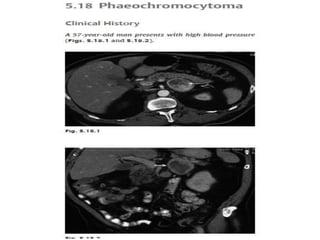

Pheochromocytoma (PHEO)

• PHEOs are rare, catecholamine-producing tumors arising from

the chromafin cells of the adrenal medulla. Their prevalence

in the general population is estimated at about 1 or 2 per

100,000 adults. The vast majority of PHEOs are sporadic

(about 86%), while the remainder (14%) are associated with

familial syndromes, such as neurofibromatosis type 1, von

Hippel-Lindau (VHL) syndrome, multiple endocrine neoplasia

type 1 (MEN1) and 2 (MEN2)

• Neoplasm of adrenal medulla.

• Usually unilateral and benign .

• C/F—paroxysmal headache, palpitation, tachycardia,

perspiration,

• HTN as tumor secretes catecholamines.

• Clinically suspected in younger patient with hypertension.

• Rule of 10 : bilateral in 10%

• malignant in 10%

• extraadrenal in 10%

• multicentric in 10%

• familial in 10%

• The main clinical feature is hypertension, which is

paroxysmal in 48% and persistent in 29%, while 13%

of the patients are normotensive. Besides

hypertension, a common triad of symptoms

comprises attacks of headaches (80%), palpitations

(64%) and diaphoresis. Other manifestations

frequently misdiagnosed are those related to

endocrine gland pathology (CS, hypercalcemia,

diabetes mellitus, thyroid carcinoma) or

cardiovascular episodes (such as shock, myocarditis,

dilated cardiomyopathy, cardiac arrhythmias)